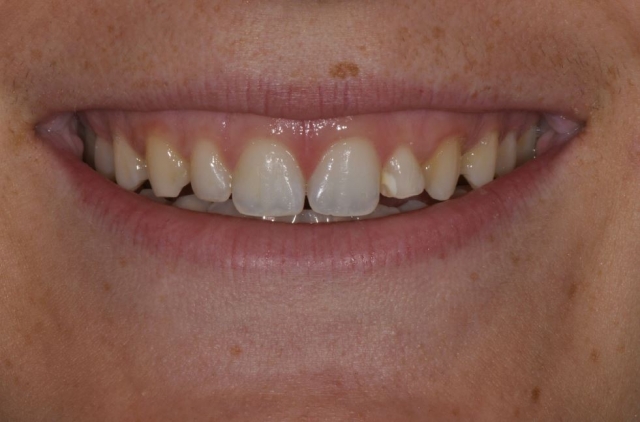

I’d like to introduce you to two patients in my practice. Caroline is a healthy, 23-year-old patient. She has a retained primary lateral incisor at tooth #10 that is decalcified and unesthetic. The tooth has undergone bone replacement and root resorption. As a result, it’s ankylosed but has acceptable bone and adequate facial prominence. An immediate implant and immediate provisional are considered the ideal treatment for replacement.

Karen is 64 years old, and her medical history is non-contributory. She, too, requires an implant at tooth #10 because of a tooth fracture from mastication. The existing tooth was deemed non-restorable. There is no periapical infection and a healthy periodontium. An implant was planned as the replacement treatment.